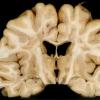

1A1 MS (Case 1) Cort Plaques A3 copy

1A2 MS (Case 1) Cort Plaques A7

1C1 MS (Case 1) Cort Plaques H&E (2) copy

1C2 MS (Case 1) Cort Plaques (block A24) H&E 2X